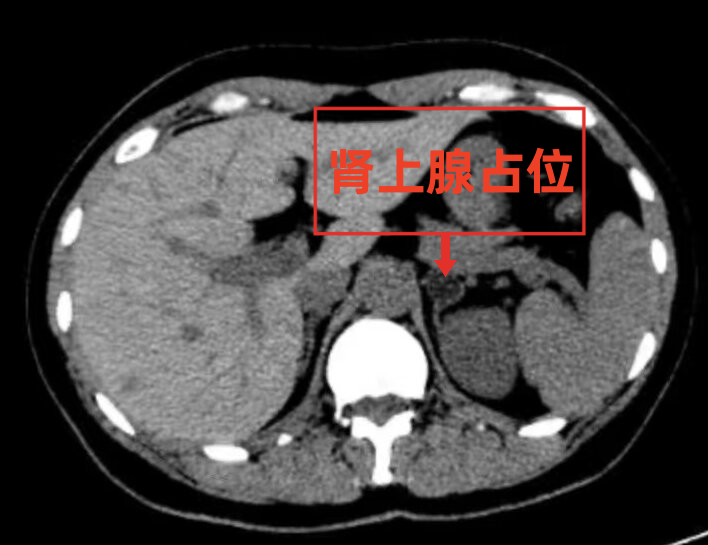

原发性醛固酮增多症是肾上腺皮质或异位肿瘤分泌过量的醛固酮激素,引起以高血压、低血钾、低血浆肾素活性和代谢性碱中毒为主要表现的临床综合征。主要表现为过量分泌的醛固酮作用于肾远曲小管醛固酮受体,造成钠钾交换增加、钠水潴留、高血压、低血钾、代谢性碱中毒。近日,36岁的吴女士(化名),因长期头晕、乏力来我院就诊,此前,其在外院检查为高血压、低血钾,内科药物治疗1年多,但效果欠佳,本人也未引起重视。我院泌尿外科门诊医生初步判断为继发性高血压,经可治愈性高血压筛查,明确诊断为原发性醛固酮增多症——醛固酮腺瘤(左侧肾上腺),与患者详细沟通后,在全麻下进行了腹腔镜下左侧肾上腺切除术。